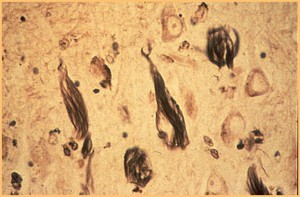

A 55 year old woman with a 10 year history of HIV infection comes to her physician after having trouble moving the left side of her body. She fears she may have had a stroke. Additionally her husband states that her behavior has been strange for the past few months and she has trouble remembering things. A brain biopsy is taken after the MRI fails to reveal an area of ischemia. Based on the histologic sample below (contents of macrophages in neural tissue), what might her diagnosis be?

HIV infection causing neurological changes:

Dementia associated with HIV may be related to actions of cytokines released by macrophages (front) in response to HIV virus infection of these cells.

- HIV in the brain is characterized histologically by the presence of perivascular multinucleated giant cells that have been shown to contain HIV.